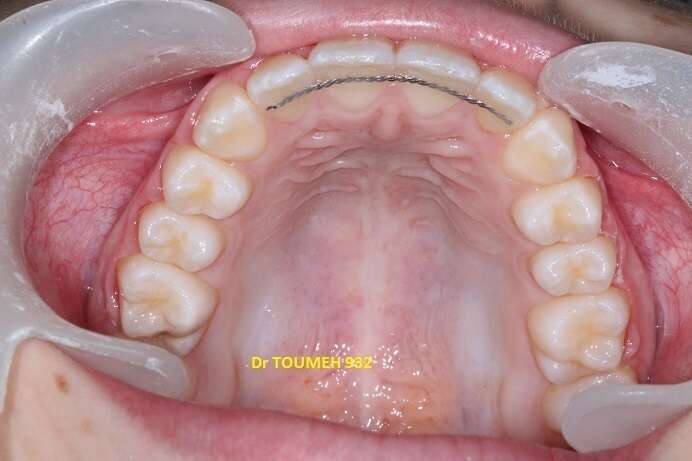

Avant

Après